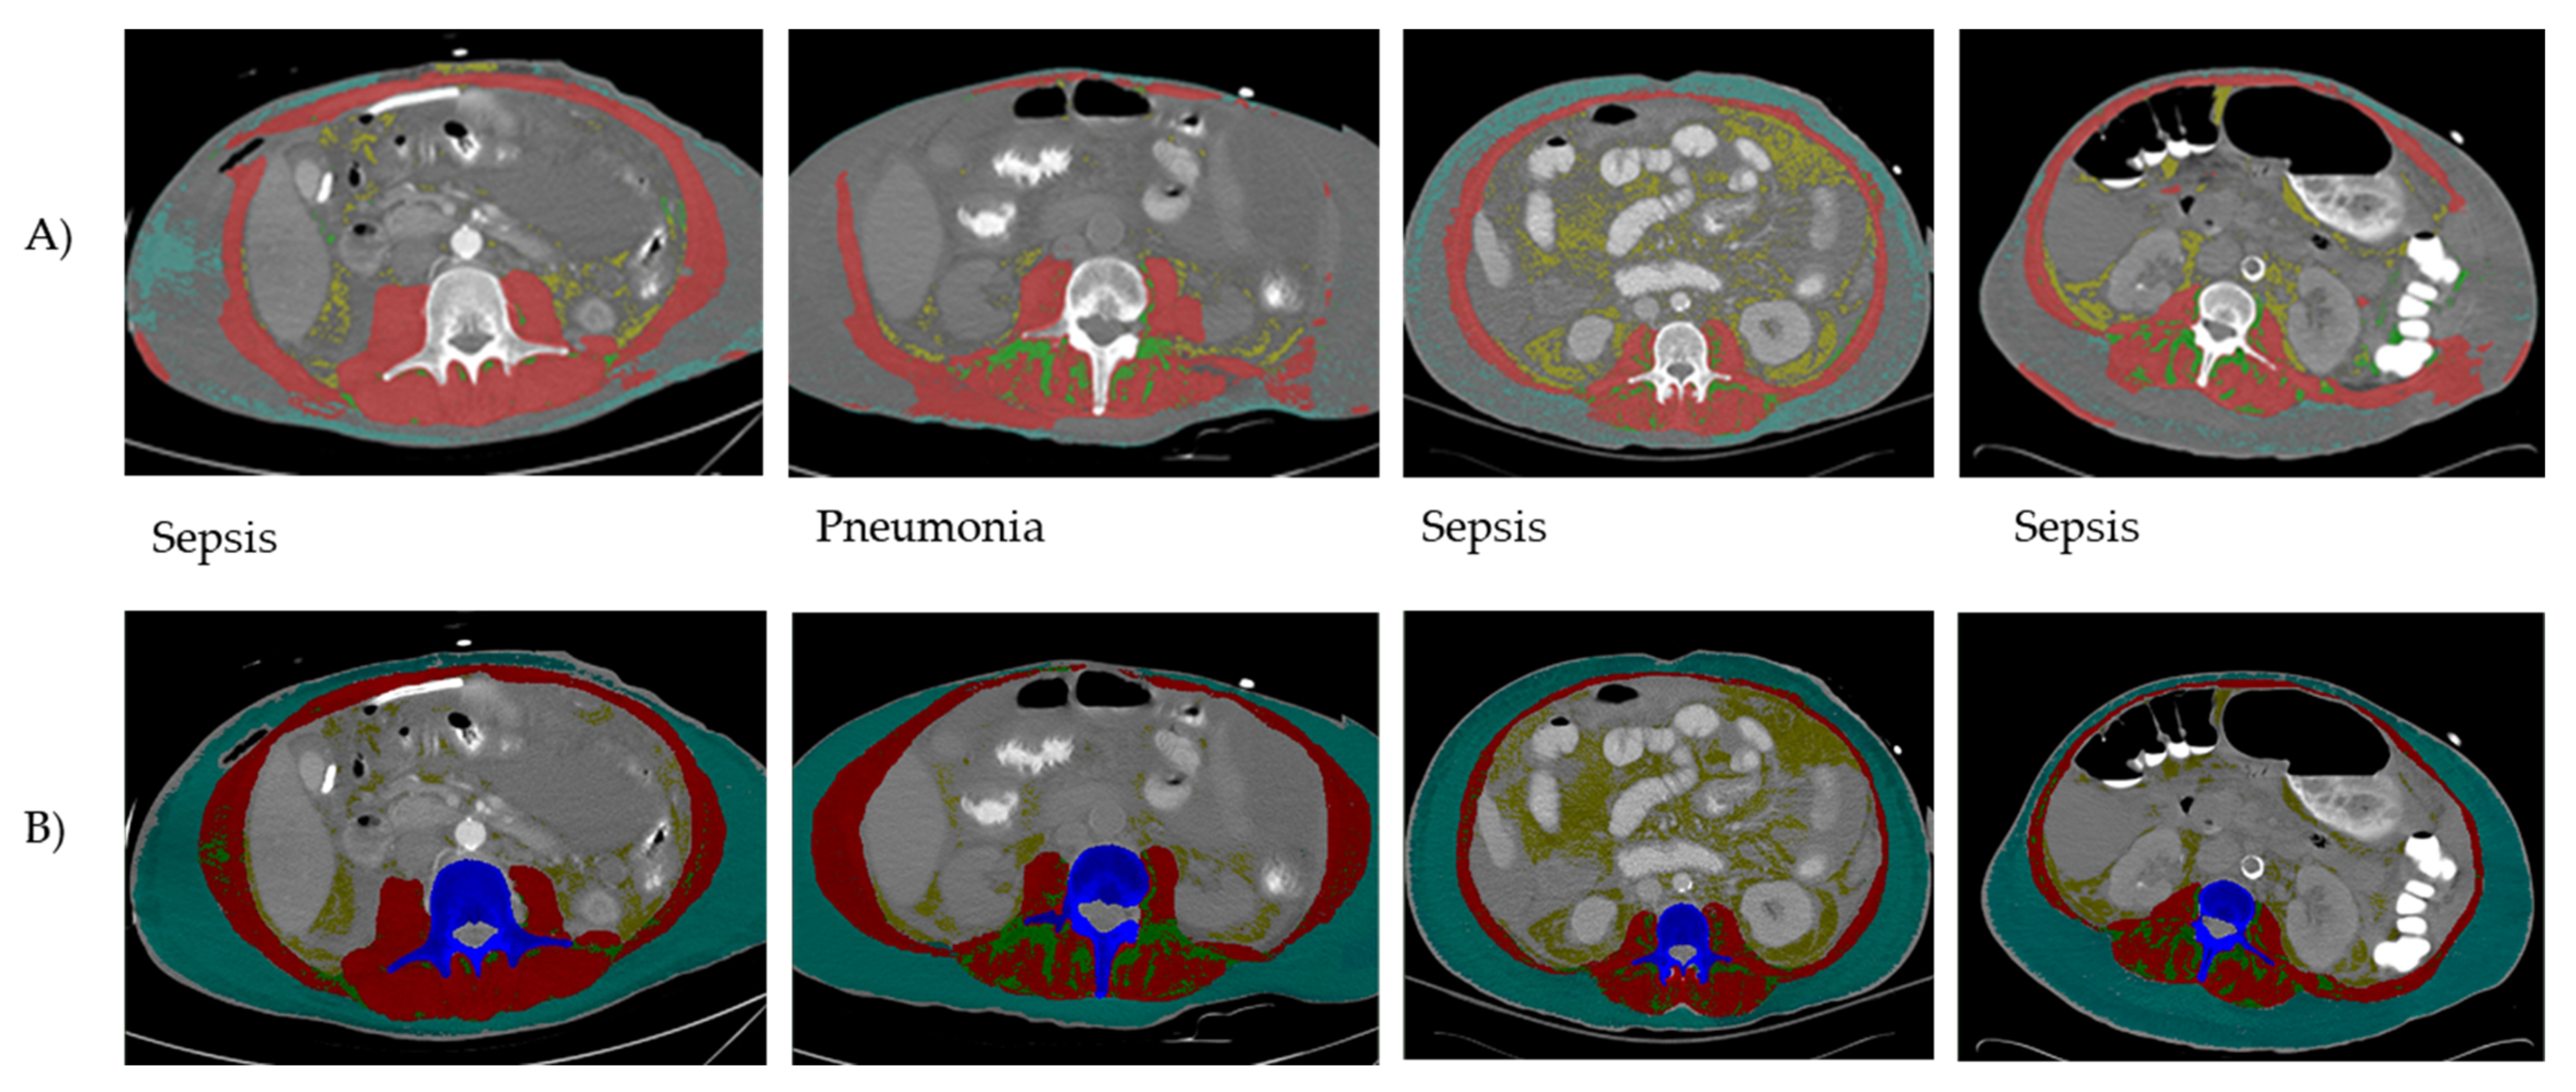

2.2. SliceOmatic Plus ABACS Analysis (Reference Method)

2.3. AutoMATiCA Analysis (Test Method)